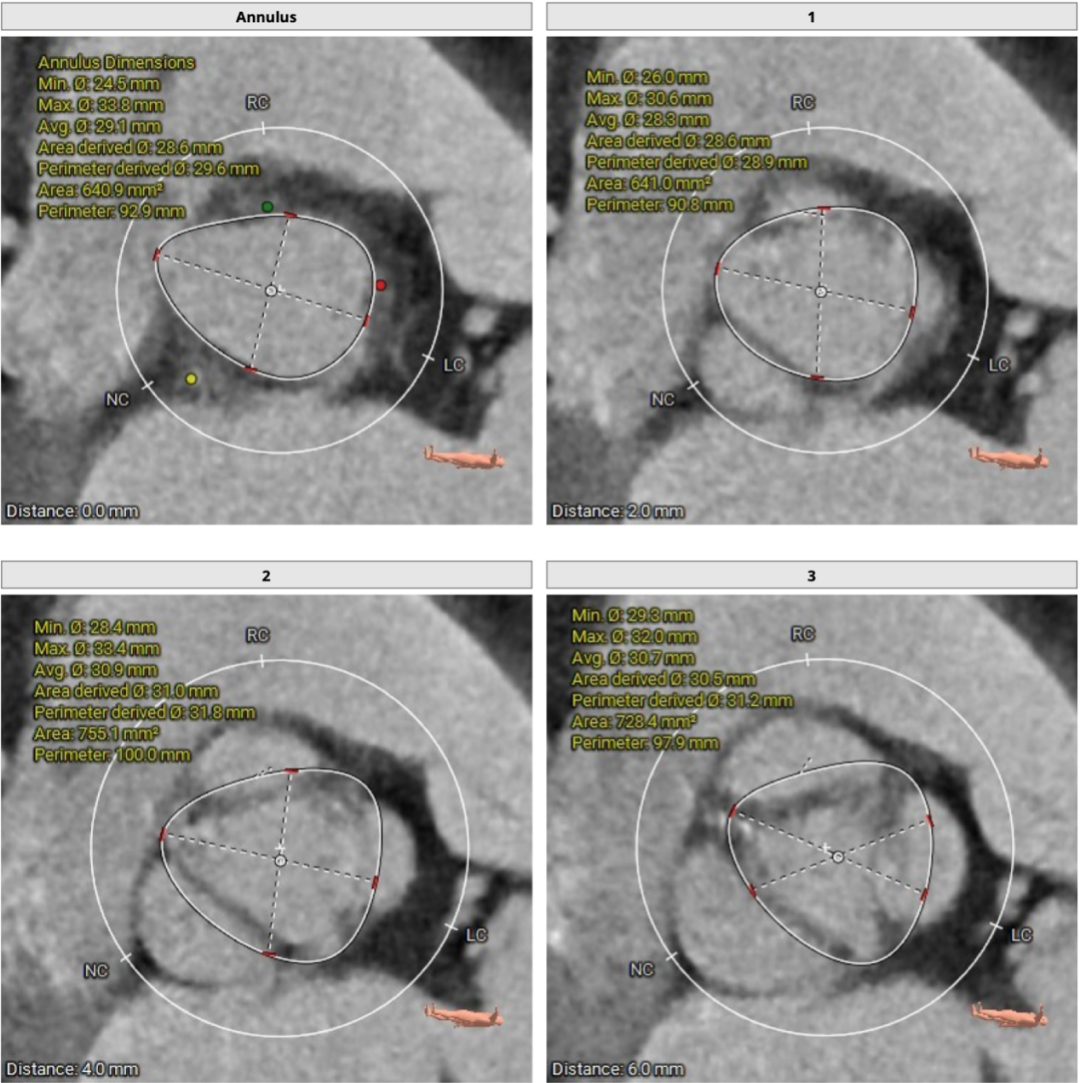

CT分析

患者主动脉瓣三叶式,瓣叶基本等大,窦部增宽,瓣叶增厚,瓣叶游离缘轻度钙化。主动脉瓣环周长折算直径约29.6mm,瓣环周长为92.9mm。

29mm瓣膜植入效果